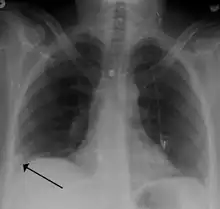

- Chest X-rays are often done on people with shortness of breath to help rule out other causes, such as congestive heart failure and rib fracture. Chest X-rays in PE are rarely normal,[70] but usually lack signs that suggest the diagnosis of PE (for example, Westermark sign, Hampton's hump).

Segmental and subsegmental pulmonary emboli on both sides- CT pulmonary angiography showing a "saddle embolus" at the bifurcation of the main pulmonary artery and thrombus burden in the lobar arteries on both sides

Pulmonary embolism (white arrow) that has been long-standing and has caused a lung infarction (black arrow) seen as a reverse halo sign